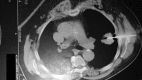

Re-biopsy after relapse of targeted therapy. T790M after epidermal growth factor mutation, where and why based on a case series

Guidelines for the treatment of non-small cell lung cancer adenocarcinoma positive in epidermal growth factor mutations indicate tyrosine kinase inhibitors. There are currently three tyrosine kinase inhibitors that can be used as first line treatment: gefitinib, erlotinib and afatinib. Regarding erlotinib and afatinib dosage can be modified in the case of severe adverse effects. In the case of disease relapse investigation for T790M mutation has to be made either with re-biopsy or liquid biopsy and osimertinib has to be administered when T790M is diagnosed. Based on a case series we indicate which is the best approach for T790M mutation.